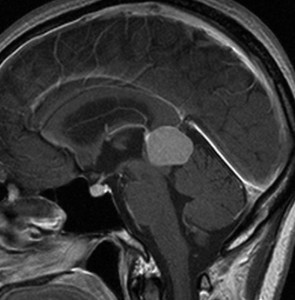

30代の女性に発生した髄膜腫です,一見すると松果体細胞腫と見分けはつきません。右の画像に見られるように典型的な中脳水道狭窄を生じていました。

軽度の閉塞性水頭症もありますが,頭痛も無く無症状なので経過を観察しました。髄膜腫だと診断できるのは,右の画像で見られるようにガレン大静脈が右側に偏っているからです。松果体細胞腫の場合は,ガレン大静脈は上方に変位します。

1年間経過観察したら水頭症が進行して脳室が拡大,腫瘍のサイズも大きくなりました。右側の画像で見られるようにガレン大静脈の左側のテントの下面から発生した髄膜腫でした。

左は手術直後の画像です,手術は左側のテント下面を見るために,後頭部経テント法 OTA occipital transtentorial approach で,小脳テントの左側を切断して腫瘍を全摘出しました。右側は6年後の画像ですが,腫瘍再発はありません。